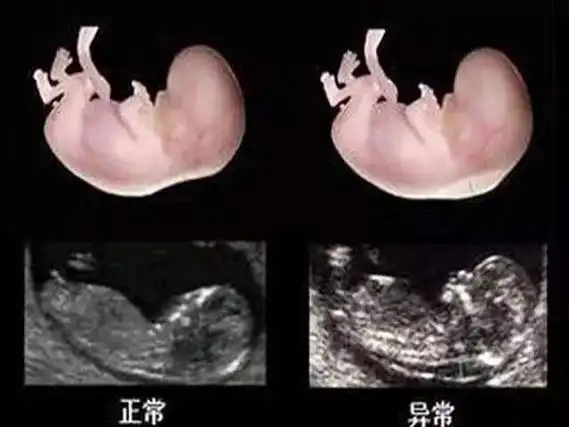

怀孕3个月胎儿变化大:nt图能看胎儿性别?别说,还真有些门道_男女

12周胎儿男女生殖图区别图